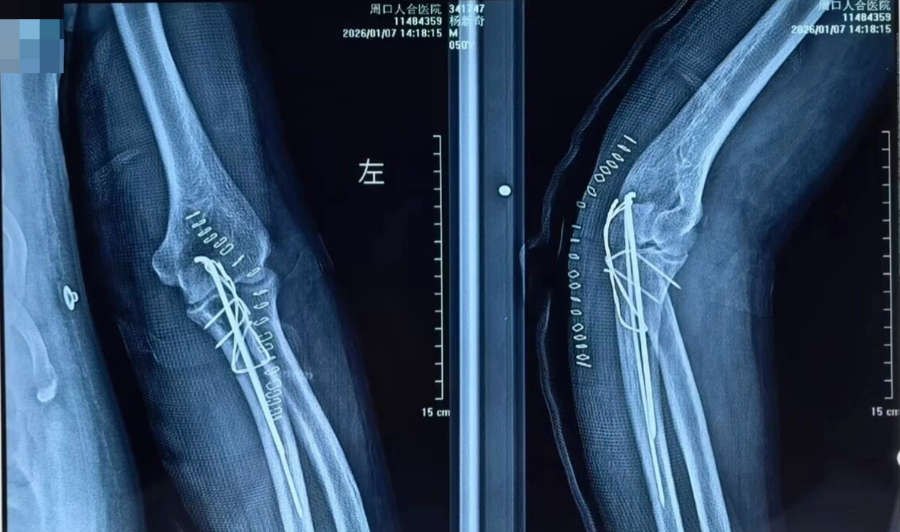

术中

抢救团队凭借丰富的创伤救治经验,在黄金时间内完成伤情评估与抗休克治疗。随后为患者施行骨折复位外固定、髓内钉内固定、解剖钢板内固定等关键手术治疗。手术过程顺利,患者出血得到有效控制,骨折部位获得稳定固定,术后生命体征平稳,安全转入ICU接受进一步监护与支持治疗。